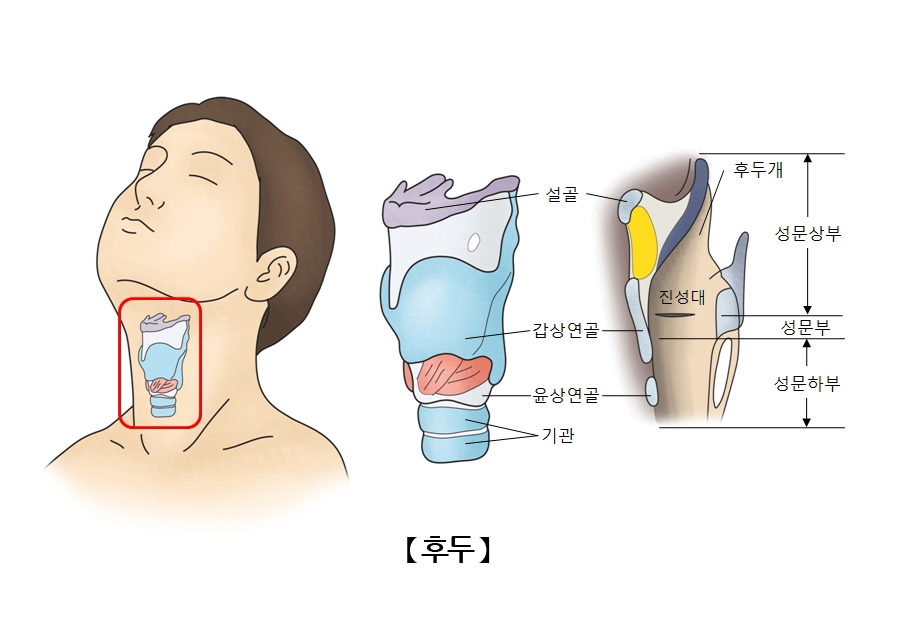

후두를 구성하는 연골. 자료 : 서울아산병원

병원은 홍군이 삼킨 어금니가 소화기관이 아닌 기관지에서 발견된 이유로 ‘후두개 연골’의 기능을 꼽았다.

목 안의 기도와 식도의 교차로에 위치한 후두는 여러 종류의 연골로 구성돼 있는데, 이중 위쪽에 위치한 후두개 연골은 후두부를 여닫는 뚜껑 역할을 한다.

얇고 탄력이 있는 후두개 연골은 음식물을 삼킬 때 기도 입구를 덮어 음식물이 기도로 들어가는 것을 막는다. 반면 호흡을 하거나 말을 할 때는 기도 입구를 열어 공기가 들어가도록 한다.

병원 측은 “홍군이 어금니를 뽑은 뒤 몸부림을 치다 어금니가 후두를 거쳐 기관지로 들어갔을 수 있다”고 짚었다.